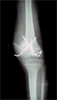

Post

Op

Had opening wedge with Translation done using Ilizarove external fixator

Progress

Good correction on Xrays with bone formation at osteotomy